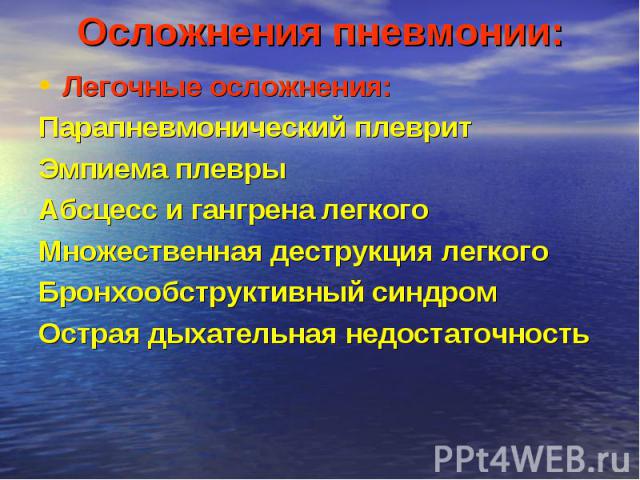

Медицинская тема: легочные осложнения при пневмонии